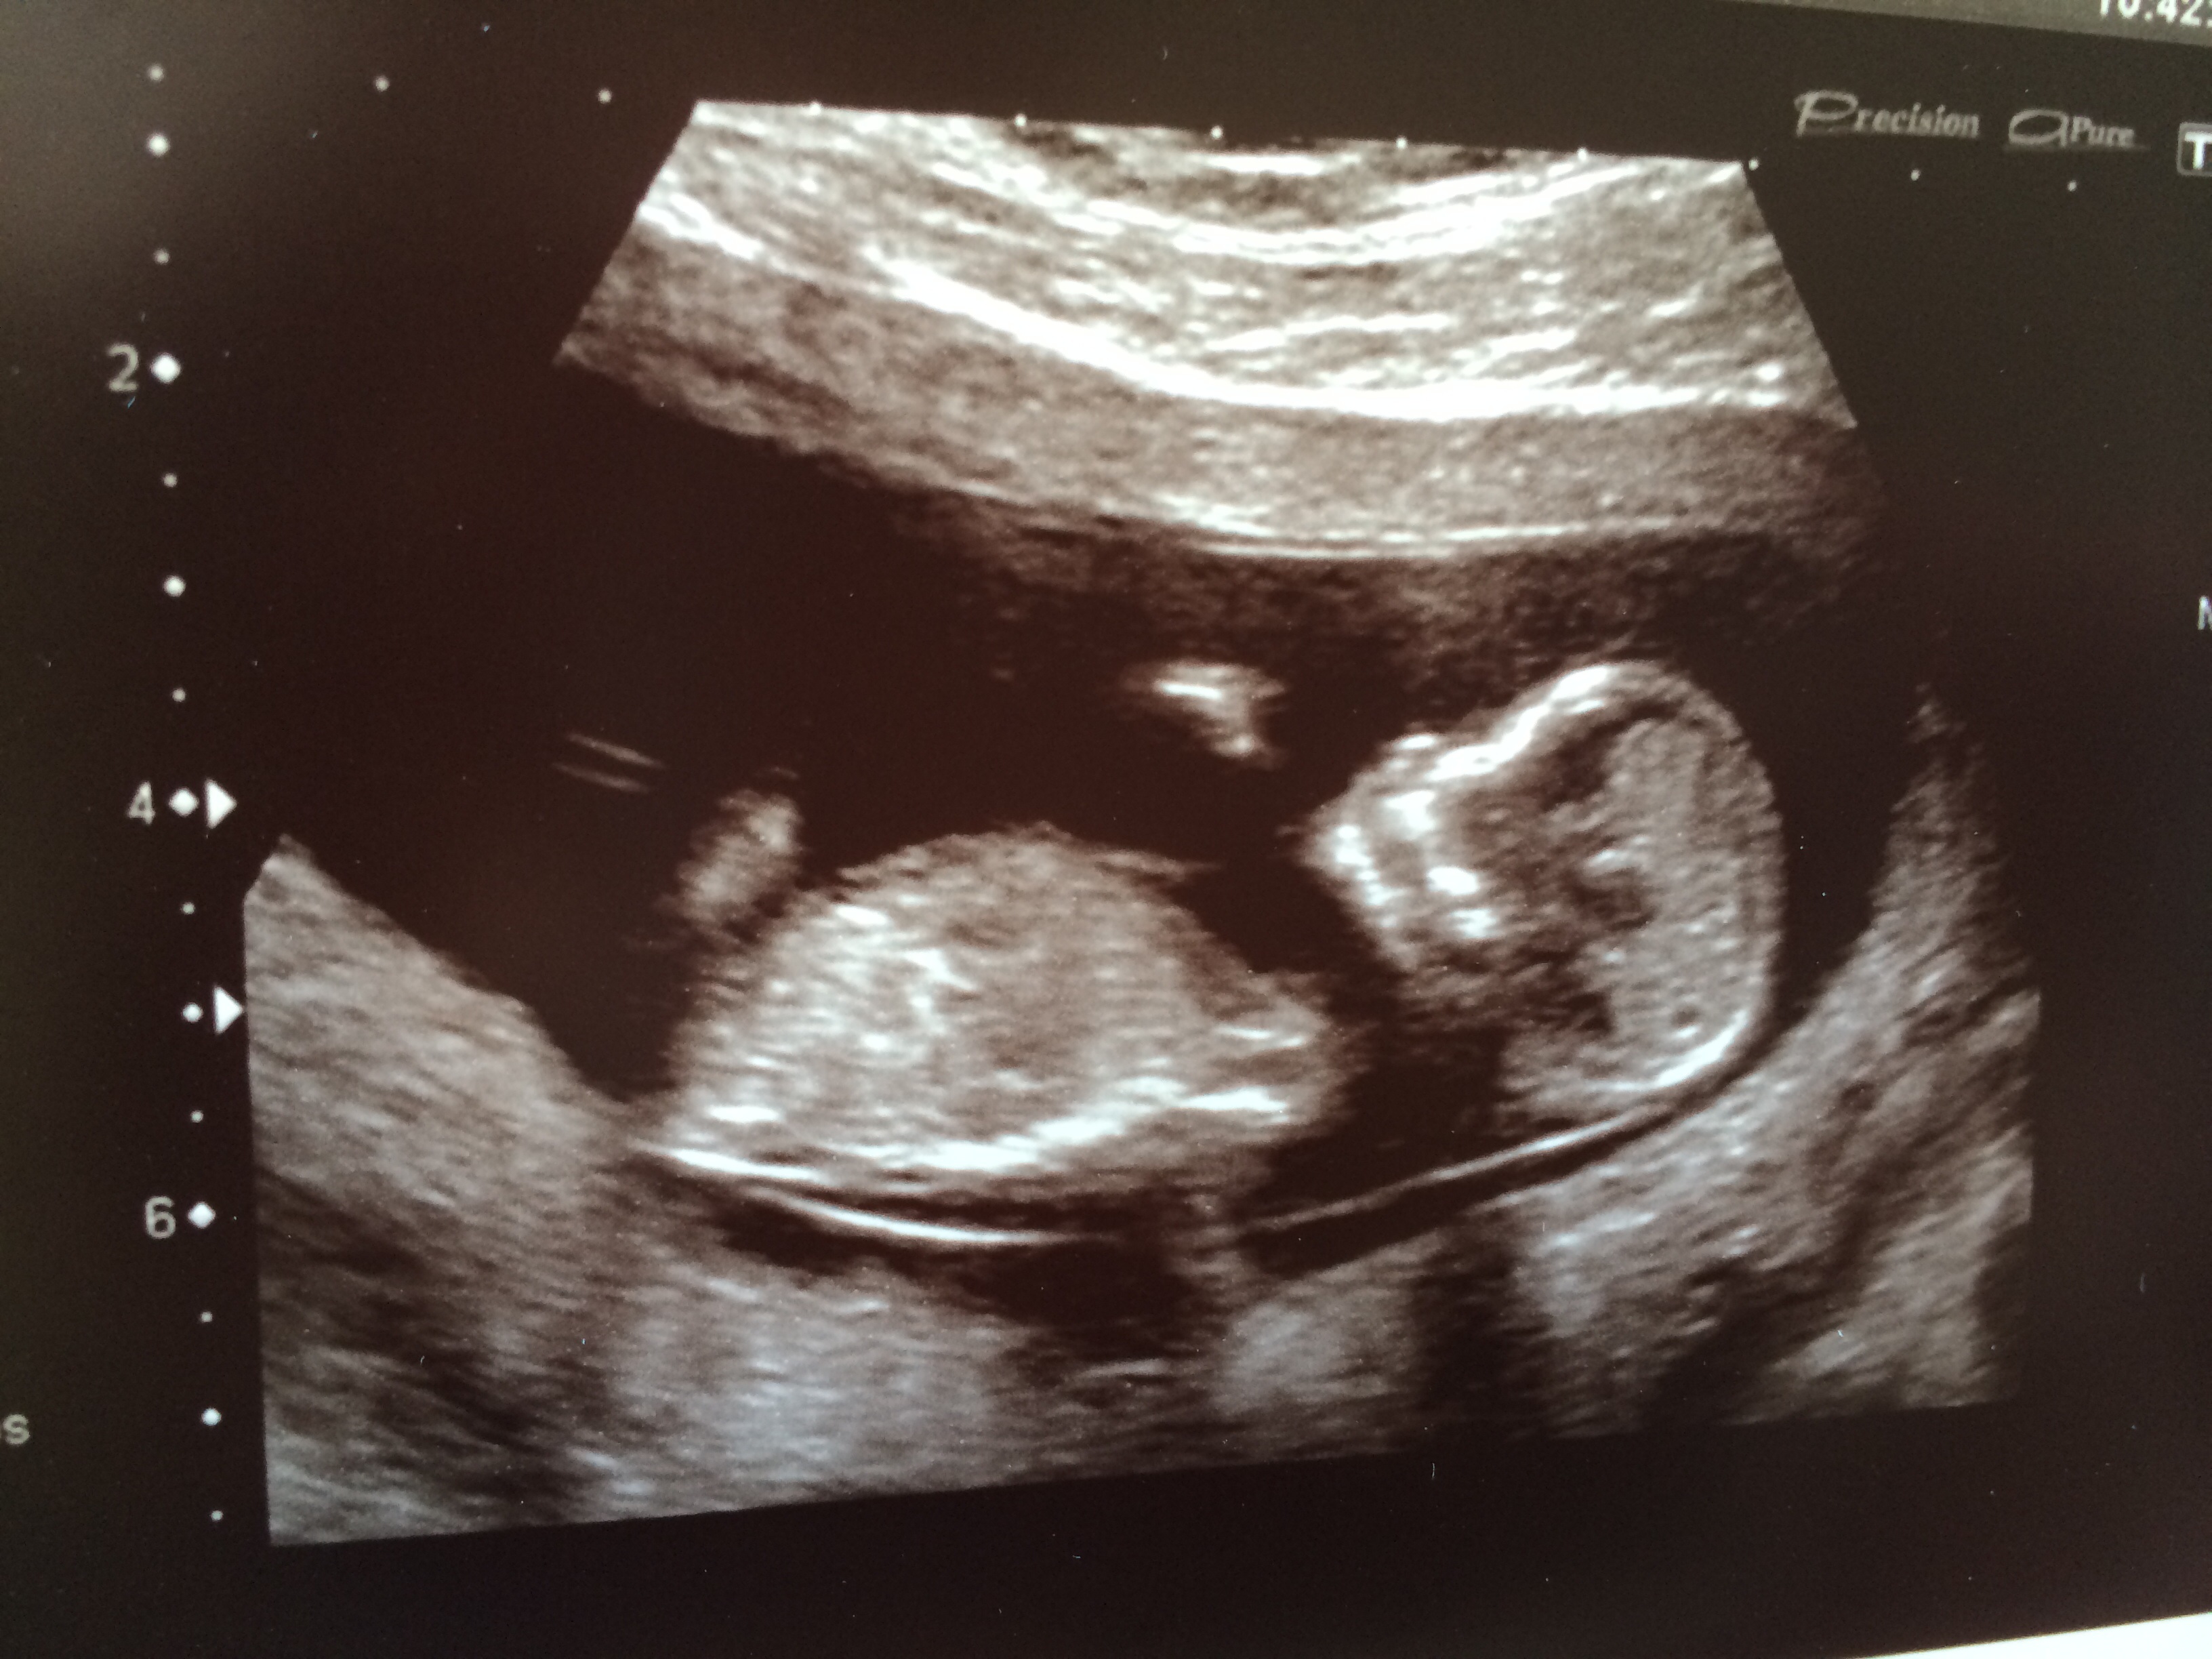

First pic is at 7+6, second two are today at 12+5 - don't think I see a nub, but any guesses are very welcome!! TIA ladies :)

I (Personally) don't see a nub, but what a cute baby! Good Luck!

No nub, but beautiful baby!!